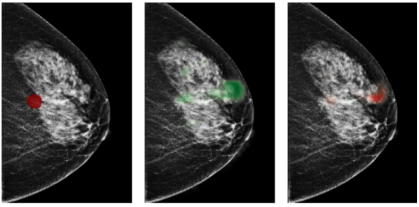

To extract information from image patches, we train a deep convolutional neural network (DCNN) to classify image patches of 256256 pixels as one of the four classes: “malignant”, “benign”, “outside” and “negative.” Malignant and benign patches are cropped from windows that overlap with the segmentation of a malignant lesion or benign tissue. Besides cropping image patches that overlap with the annotations, we sample patches that have no overlap with any lesion (“outside”), as well as patches from breasts without records of biopsy (“negative”). The inclusion of these additional data is intended to regularize the model similarly to data augmentation. Examples of patches from each class are shown in Figure 3.

![]() |

|

| a | b |

| c | d |